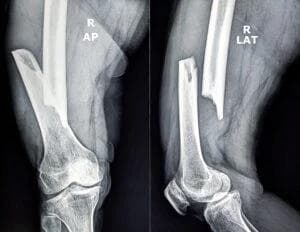

- X‑rays and CT scans showing the break pattern and any displacement

- Trial Preparation – Ready to present X‑ray visuals and orthopedic testimony if carriers refuse fair terms.